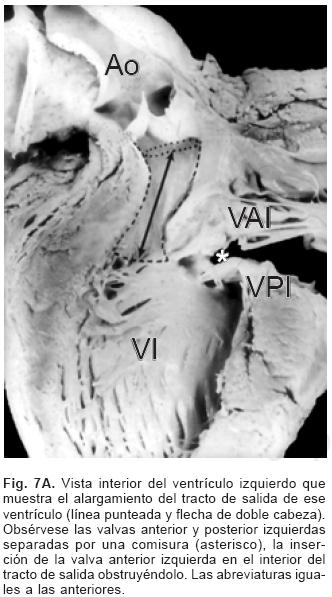

La anatomía básica de los 2 tipos de DSA–V fue la misma. Todos presentaron anillo fibroso A–V común, reducción de la distancia A–V–ápex e incremento de la distancia ápex –válvula aórtica, el tabique ventricular estuvo excavado (Figs. 4 y 6C), el anillo fibroso mostró dilatación anteroposterior, desencuñamiento aórtico, alteración en el esqueleto fibroso del corazón consistente en un anillo fibroso A–V común, ausencia del septum membranoso y persistencia de la continuidad entre la válvula aórtica y la válvula A–V común o válvula A–V izquierda (Fig. 6D), desviación anterior del tracto de salida del ventrículo izquierdo (Figs. 4 y 6C) y en dos especímenes obstrucción de éste por inserción en su interior de la valva anterosuperior izquierda (Fig. 7A). En un espécimen con una válvula A–V común se desarrolló una banda anómala de miocardio entre la pared libre y el tabique ventricular, lo que separó el componente derecho de la válvula A–V común en dos orificios valvulares (Fig. 7B). Las alteraciones asociadas se consignan en la Tabla III.

Debido al DSA–V y a la deficiencia del tabique ventricular, éste muestra un aspecto excavado con disminución de la porción de entrada y alargamiento del tracto de salida; cuando se divide el valor de la primera entre el de la segunda el índice obtenido es inferior a la unidad y entre más corta sea la porción de entrada más larga es la salida del ventrículo izquierdo.2,9 En un corazón normal el coeficiente es muy cercano a la unidad ya que ambas distancias casi son equidistantes. Este hecho tiene una gran importancia ya que el alargamiento del tracto de salida y su desplazamiento anterior condiciona un estrechamiento en el mismo y en ciertas ocasiones la valva anterior izquierda puede enviar sus cuerdas tendinosas hacia el interior de dicho tracto, lo que produce obstrucción subaórtica como ocurrió en dos corazones de esta serie. Se ha referido en la literatura que aquellos casos con tracto de salida muy alargado presentan riesgo potencial de obstrucción postquirúrgica.9,24 El alargamiento del tracto de salida y su desplazamiento anterior constituyen la base anatómica del signo angiográfico de "cuello de ganso", patognomónico de esta cardiopatía.25